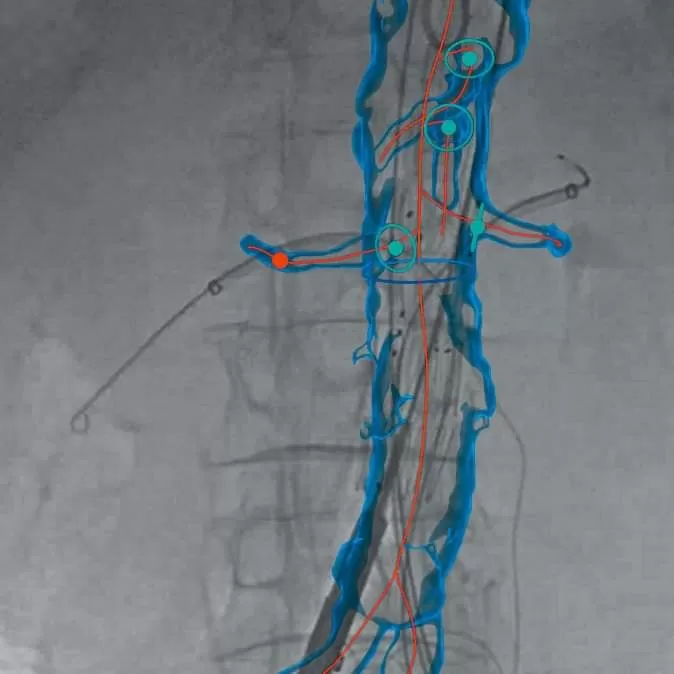

➡️ They allow for the planning of the therapeutic approach with speed and ease but also offer faster navigation during intravascular invasive techniques, providing the ability to fuse images with 3D fusion techniques, offering direct control, information and speed during intravascular interventions.

➡️ The EndoNaut system in combination with a high-tech digital X-ray C-arm (such as the Ziehm Vision RFD HE) and a high-quality low-dose X-ray surgical table, is a cost-effective, viable and reliable alternative to hybrid surgeries with fixed-imaging systems, offering excellent ergonomics with a small learning curve.